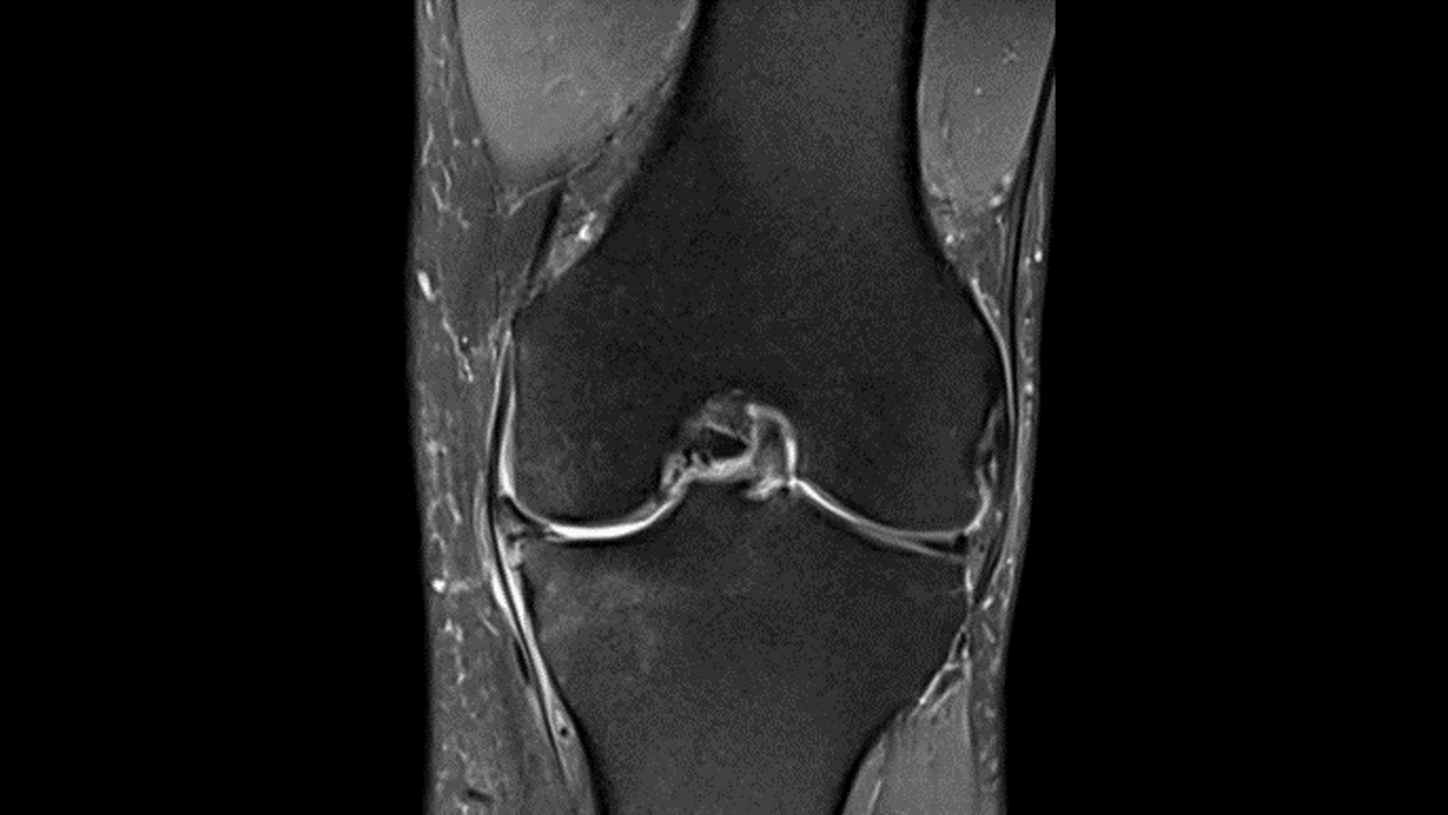

Key investigation areas for MRI are soft tissue areas like brain, abdomen, vessels, ligaments, cartilages or muscles.

Fig3: Courtesy of Radiologische Gemeinschaftspraxis, Halle/Saale, Germany